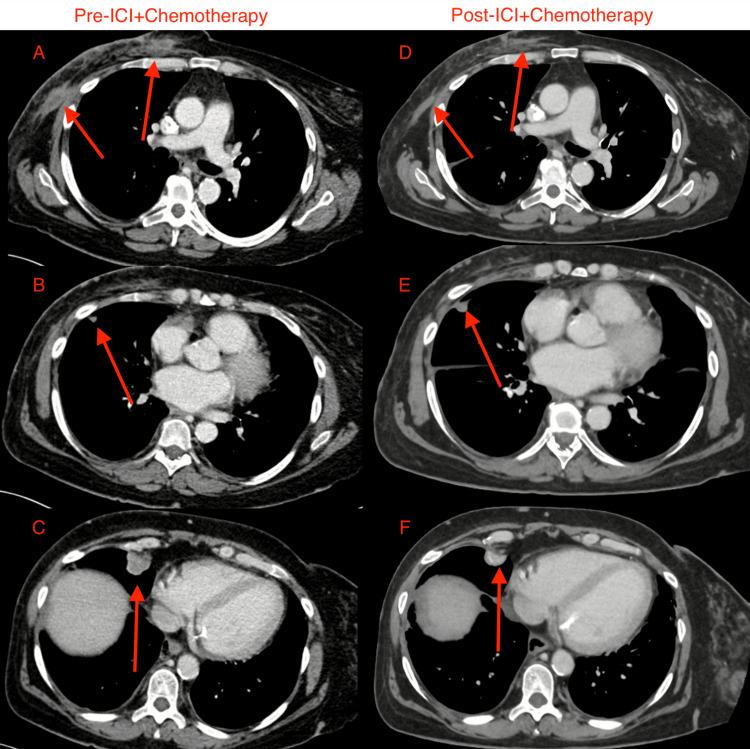

Immune checkpoint inhibitors (ICIs) are fundamental to the management of hematologic and solid organ malignancies, and indications for their use are rapidly increasing. Patients with preexisting autoimmune diseases are often excluded from clinical trials involving ICIs due to the risk of exacerbating the underlying autoimmune condition. The lack of trial-level safety data limits the use of these therapies in real-world patients with autoimmune disease. We present a case series of two patients with preexisting autoimmune diseases who received immunotherapy for their malignancies, with manageable toxicities and desirable outcomes from an oncologic standpoint. We aim to contribute to the growing body of evidence suggesting that ICIs can be safely offered to selected patients with autoimmune diseases.

免疫检查点抑制剂(ICI)是血液系统和实体器官恶性肿瘤治疗的基础,其应用指征正在迅速增加。由于存在加重潜在自身免疫性疾病的风险,患有自身免疫性疾病的患者通常被排除在涉及ICI的临床试验之外。缺乏试验层面的安全性数据限制了这些疗法在患有自身免疫性疾病的真实世界患者中的应用。我们报告了一系列两例患有自身免疫性疾病的患者,他们接受了针对恶性肿瘤的免疫治疗,毒性可控,从肿瘤学角度来看预后良好。我们旨在为越来越多的证据做出贡献,表明ICI可以安全地用于选定的自身免疫性疾病患者。